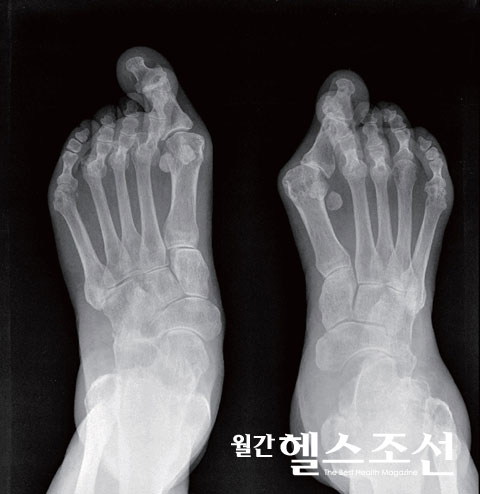

류마티스 관절염은 관절의 변형을 일으켜 극심한 통증을 일으킨다.